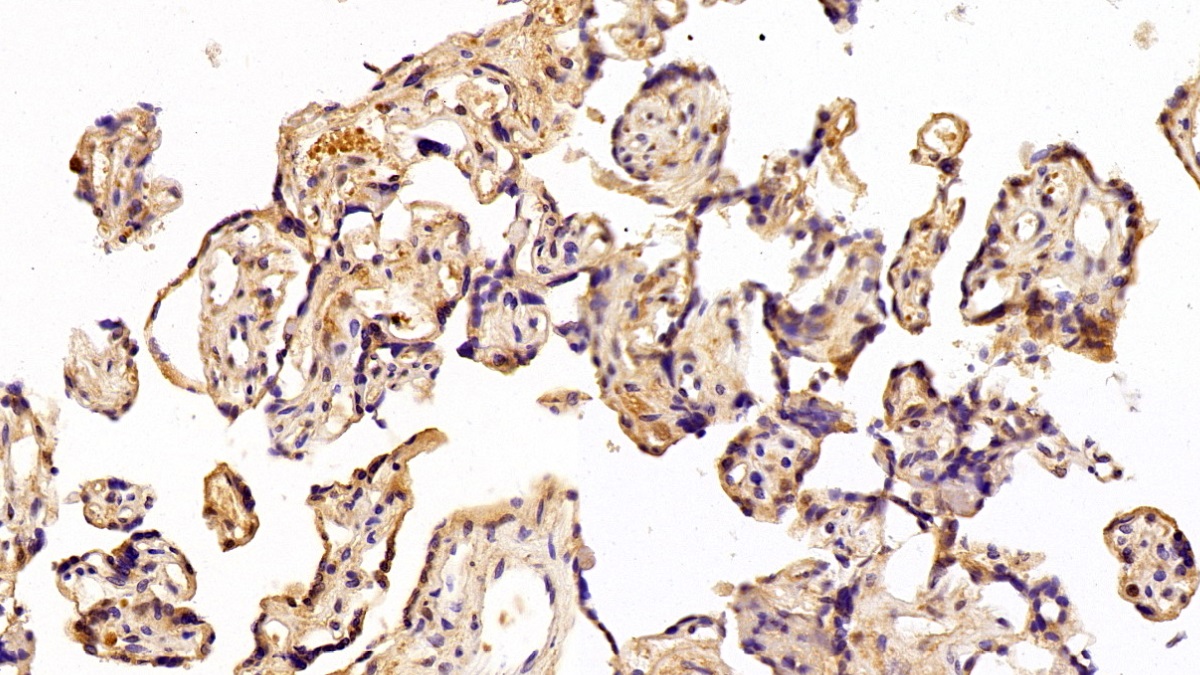

| Валидировано для | IHC WB Иммуногистохимия; Вестерн-блоттинг |

| Рекомендуемые разведения | WB: 0.2-3 мкг/мл; IHC: 2-30 мкг/мл; ICC: 2-30 мкг/мл; Оптимальное разведение определяется конечным потребителем |